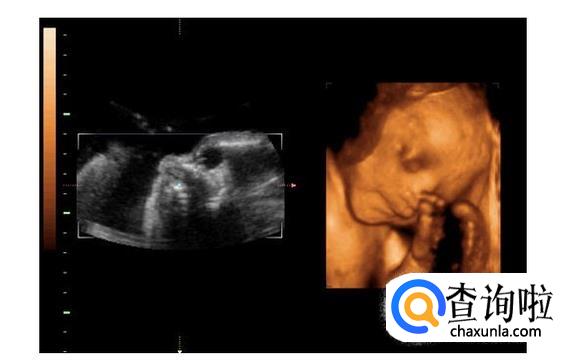

- 04

四维彩超是采用三维超声图像加上时间维度参数,可以更直观更清晰地呈现胎儿在宫内的动态图像,多方位、多角度地观察胎宝宝的生长发育情况。